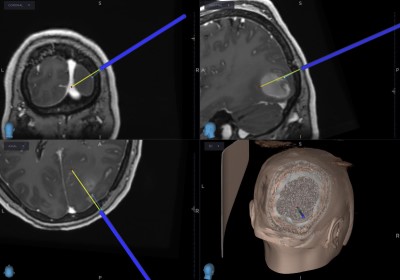

- Pre-Op

- Post-op